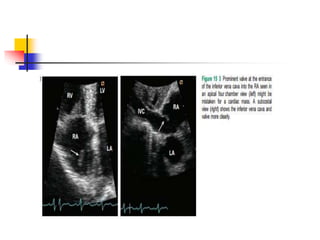

Eustachian Valve

 The eustachian valve is often misdiagnosed as an

intraatrial thrombus.

 The eustachian valve (called a Chiari network when

fenestrated) is the persistent portions of embryologic

valves of sinus venosus, which is important in utero

to direct inferior vena cava blood flow across the

fossa ovalis.

 The filamentous structures can be differentiated from

thrombus by their characteristic "insertion" into the

atrial wall.

 In echo, leaf-like linear structure is seen at the

junction of IVC and RA.

 RV inflow view, subxiphoid view, and TEE is

diagnostic because such windows can visualize both

Eustachian valve and IVC in the same imaging plane.

 Occasionally, prominent Eustachian valve appears to

divide RA into two chambers making apparent cor

triatriatum dexter .

 Such condition is hemodynamically insignificant in

most adults because the septation by Eustachian

valve is generally incomplete.